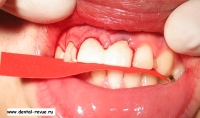

4. Рассечение круговой связки перитомом.